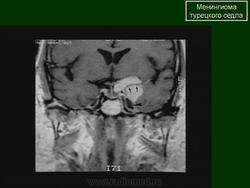

Образования селлярной области.

Образования и заболевания селлярной области.